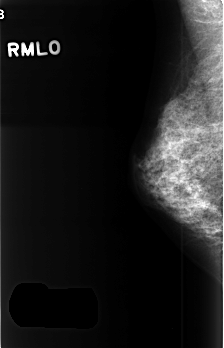

C_0368_1.RIGHT_MLO

RIGHT_CC LINES 4576 PIXELS_PER_LINE 2896 BITS_PER_PIXEL 12 RESOLUTION 50 NON_OVERLAY

RIGHT_MLO LINES 4520 PIXELS_PER_LINE 2904 BITS_PER_PIXEL 12 RESOLUTION 50 NON_OVERLAY